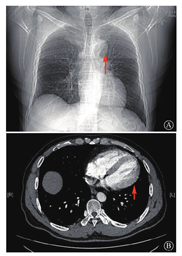

患者男性,45岁,因"查体发现肺部阴影9个月"于2019年12月10日入院。患者自诉无明显不适,未行系统诊治。既往无特殊病史,无家族性疾病史。入院查体:血压:129/74 mmHg,心率:59次/min,窦性心律,律齐,触诊心尖搏动位于胸骨左缘第五肋间锁骨中线,听诊双肺呼吸音清,未闻及干湿性啰音,各瓣膜听诊区未闻及杂音。入院12导联心电图示窦性心动过缓,心率59次/min,ST-T改变(图1)。胸部X线片示心脏左偏,主肺动脉间无肺组织影,左肺毛玻璃影(图2A);胸部CT未见心包影,左肺上叶多发毛玻璃结节(图2B)。超声心动图未见明显异常。术前诊断:肺部结节,遂行胸腔镜下肺部结节切除术。术中患者右侧卧位,取左胸第4肋间、腋中线第7肋间作为腔镜入路,探查见胸膜无粘连,完全性心包缺如(图3),行左肺上叶切除术。病理诊断:以贴壁生长为主的肺泡上皮源性肿瘤,微浸润性腺癌(2 cm×1.6 cm),原位腺癌(0.8 cm),均未侵及脏层胸膜,未累及支气管断端。肺癌多基因检测:EGFRExon21 L858R阳性突变。术后诊断:肺部占位,先天性心包缺如。复查超声心动图:右室前壁、剑突下右室游离壁未见心包样回声,右室前壁活动度明显增大。术后6个月随访,患者胸部CT未见新发病灶、无胸腔积液,无明显临床症状。

A:胸部正位X线片示心脏左偏,如箭头所示,主肺动脉间无肺组织影;B:胸部CT纵隔窗,如箭头所示,未见心包影

医学影像学的进步,为明确先天性心包缺如的诊断提供了手段。1971年,Morgan等[11]报道了6例患者,证实完全性心包缺如可通过体格检查、心电图及胸部X线片等进行临床诊断。体格检查可触及心尖搏动点明显异位,可于腋前线或腋中线触及,并报道了1位77岁的老年患者的心尖搏动点位于左肩胛中线[12,13]。听诊可闻及心脏基底部的收缩中期杂音,或不能确定起源的收缩期杂音。此外,由于本病常合并右束支传导阻滞,可闻及第二心音分裂增强。心电图表现可见窦性心动过缓及电轴右偏或右束支传导阻滞,部分可见由于心前区左移导致的R波低平,或提示右房负荷过重的P波改变[14,15]。胸部X线片可见心脏左侧移位,左室边界扁长。由于肺组织的异位,心脏与膈之间、主肺动脉之间可见透亮影,还有一些病例可见位于主动脉弓、肺动脉之间的舌状组织[2]。